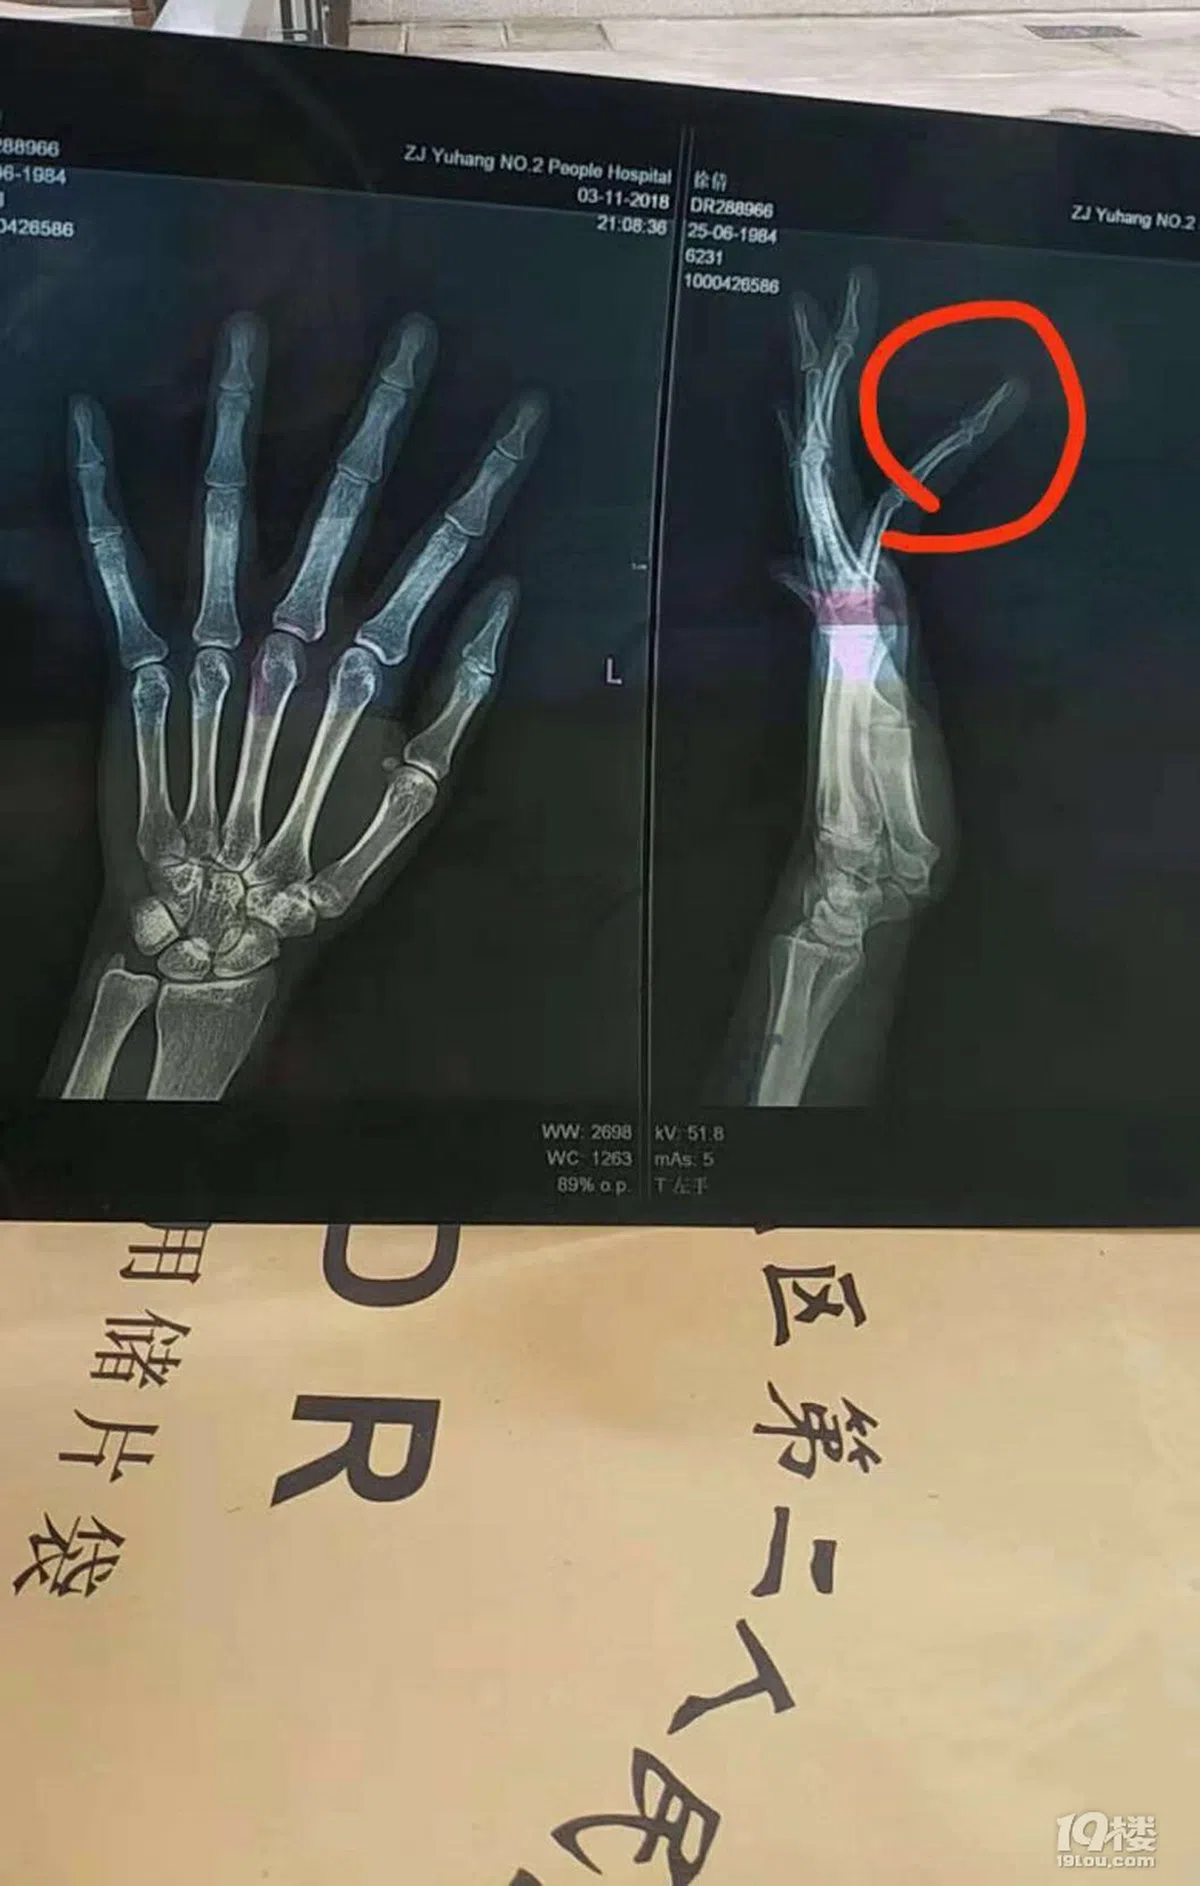

徐女士去医院检查后,发现脸上多处淤青,左手手指骨折。

“19楼”中徐女士贴出自己左手的X光片